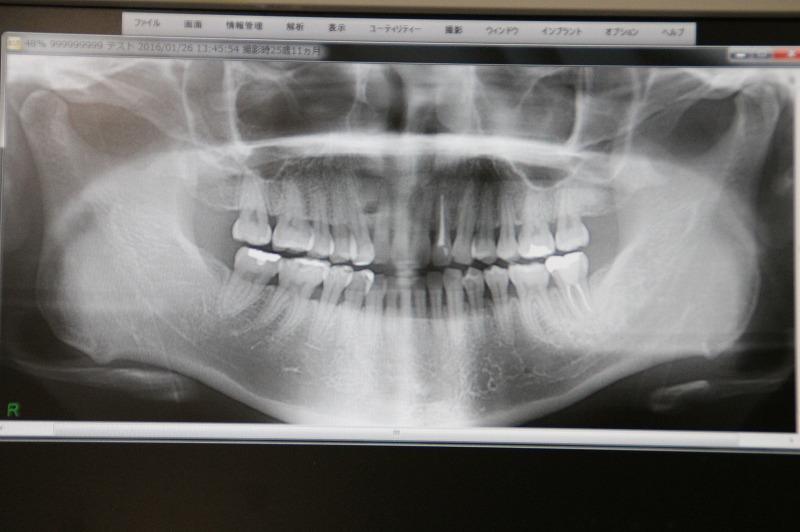

パノラマレントゲン写真

お口の中全体を1枚のレントゲン写真として撮影することができます。

大まかな歯の状態や骨の中の以上、神経の位置などを知ることができます。